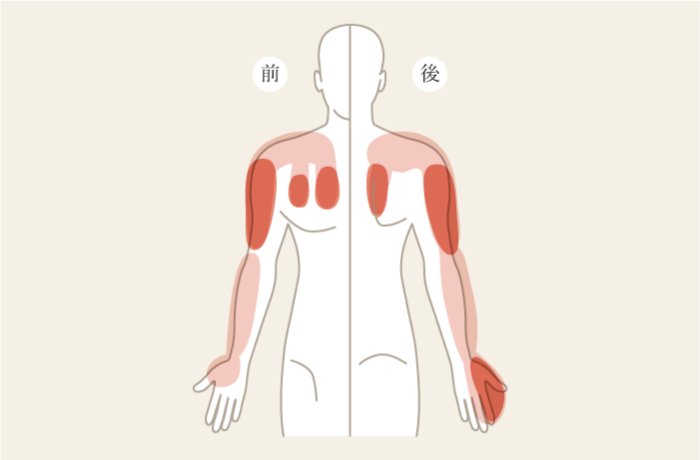

頸部の神経症状

上肢のしびれ

頸部の神経症状

上肢のしびれ

-

上肢への放散痛やしびれ、感覚障害さらには運動機能障害も引き起こされることがある